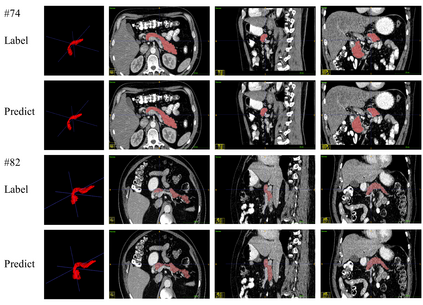

Transformer-based neural networks have surpassed promising performance on many biomedical image segmentation tasks due to a better global information modeling from the self-attention mechanism. However, most methods are still designed for 2D medical images while ignoring the essential 3D volume information. The main challenge for 3D transformer-based segmentation methods is the quadratic complexity introduced by the self-attention mechanism \cite{vaswani2017attention}. In this paper, we propose a novel transformer architecture for 3D medical image segmentation using an encoder-decoder style architecture with linear complexity. Furthermore, we newly introduce a dynamic token concept to further reduce the token numbers for self-attention calculation. Taking advantage of the global information modeling, we provide uncertainty maps from different hierarchy stages. We evaluate this method on multiple challenging CT pancreas segmentation datasets. Our promising results show that our novel 3D Transformer-based segmentor could provide promising highly feasible segmentation performance and accurate uncertainty quantification using single annotation. Code is available https://github.com/freshman97/LinTransUNet.